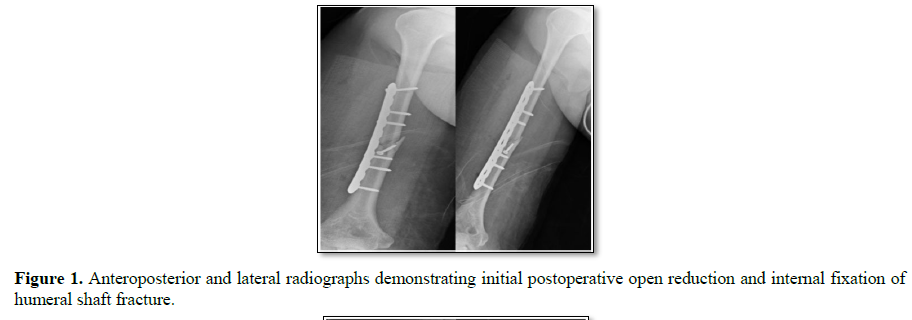

Inclusion criteria were patients >18 years of age who underwent operative internal fracture fixation. Exclusion criteria included lack of documented 25(OH) vitamin D levels during initial hospitalization, those lost to follow up before fracture union, amputation of fractured limb, cancerous bony lesions and those taking medications pre-injury that would affect bone metabolism such as bisphosphonates and teriparatide. Polytrauma patients were not excluded and each fracture was recorded and reviewed separately for union. Fracture type and patient demographics were extracted from the patient’s medical record, while operative reports were reviewed to determine the fixation method utilized. Fracture union was compared to initial postoperative films (Figure 1) and defined as the lack of visible fracture lines or presence of abundant callus/bone bridging the fracture site at three cortices or more on orthogonal postoperative radiographs (Figure 2). Union was confirmed by two separate physician reviewers. Time to union was recorded based on time from fixation to fracture union. Review of electronic medical records was performed to determine hospital length of stay, postoperative calcium and vitamin D levels, and postoperative bisphosphonate or teriparatide supplementation. Statistical analysis was performed, with means; ranges and confidence intervals calculated for continuous variables and compared using Student’s t-tests.  Fisher’s exact test was employed for increased accuracy in small proportion analysis. A significance level of P<0.05 was set as significant.